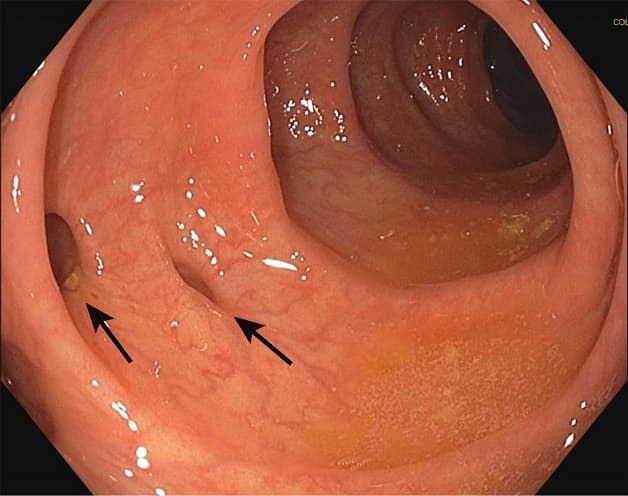

Nội soi đại tràng thường được ưu tiên thực hiện nhằm chẩn đoán chảy máu túi thừa đại tràng. Người bệnh sẽ tiến hành nội soi trong vòng 12 – 48 giờ tính từ thời điểm nhập viện, sau khi đã điều trị hồi sức cấp cứu, ổn định huyết động, loại trừ chảy máu đường tiêu hóa trên.

Nội soi đại tràng giúp xác định chính xác vị trí chảy máu tại đại tràng. Từ đó bác sĩ có thể can thiệp cầm máu cho người bệnh. Nếu người bệnh không thể thực hiện nội soi hoặc nội soi không tìm được điểm chảy máu, bác sĩ sẽ chỉ định các phương pháp khác như:

Nếu nội soi đại tràng phát hiện vị trí đang chảy máu hoặc có mạch máu lộ, bác sĩ có thể can thiệp các thủ thuật để cầm máu như:

Xử trí qua nội soi đối với chảy máu đại tràng là kỹ thuật tương đối phức tạp. Người bệnh cần được làm sạch đường ruột nhanh chóng, kiểm tra cẩn thận từng túi thừa đại tràng và xác định dấu hiệu thực sự của xuất huyết. Điều này giải thích vì sao người bệnh cần được điều trị tại các cơ sở y tế uy tín với đội ngũ bác sĩ giỏi, trang thiết bị máy móc hiện đại.

Bác sĩ có thể can thiệp qua nội soi để cầm máu trong trường hợp chảy máu túi thừa đại tràng